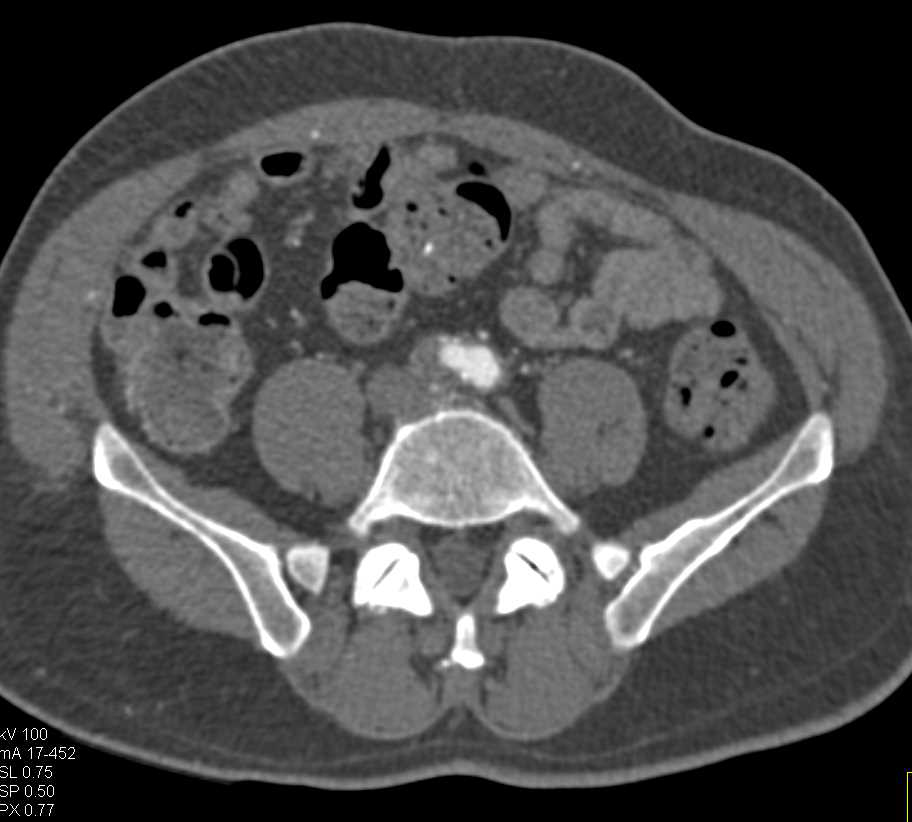

Prior Embolization of Pulmonary Arteriovenous Malformation (PAVM)